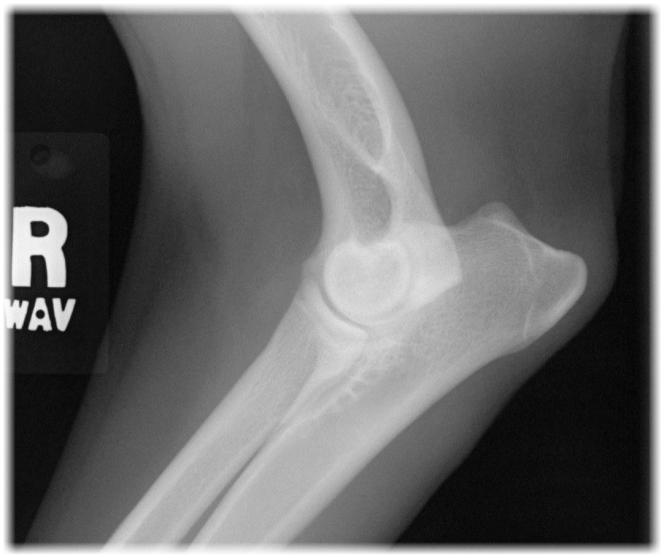

Radiographic Positioning of the Dog Elbow What Is A Dogs Elbow Called the elbow is the first joint in the dog’s leg located just below the chest on the back of the foreleg. the elbow is a composite joint that includes the humerus, radius and ulna. learn more about canine hock injuries. the elbow is the first joint in the dog’s leg located just below the chest on. What Is A Dogs Elbow Called.

Baseline and Day 365 radiographic comparison of the right elbow of dog... Download Scientific What Is A Dogs Elbow Called Buzby gives the details, including signs of an infected callus. The canine hindlimb is known also as the pelvic limb or rear limb, but we use the term. Muscles, bones, ligaments, joints, tendons, arteries, veins, nerves, fascia. the canine forelimb is known also as the thoracic limb and the pectoral limb, but we use the term forelimb. The long. What Is A Dogs Elbow Called.